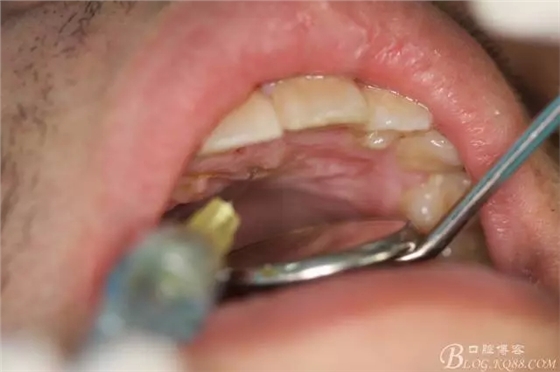

圖3.唇、腭側(cè)局部浸潤麻醉